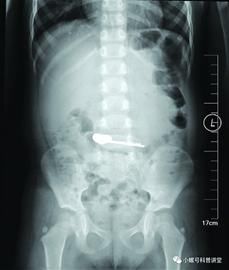

情急之下,家人赶紧带着女儿到市妇儿医院就诊。经检查发现,钻戒到了妞妞的胃里,但是因个头大、不规则,无法通过幽门排出,只好通过手术取出。市妇儿医院内镜中心主任任悦义介绍,取出钻戒的过程大约用了十来分钟,由于钻戒是不规则物体,取出时途经贲门费了一些周折,医生小心翼翼寻找角度,以防出现二次损伤。据悉,从妞妞胃里取出的这颗钻戒,是迄今为止市妇儿医院取出的最贵重的消化道异物。